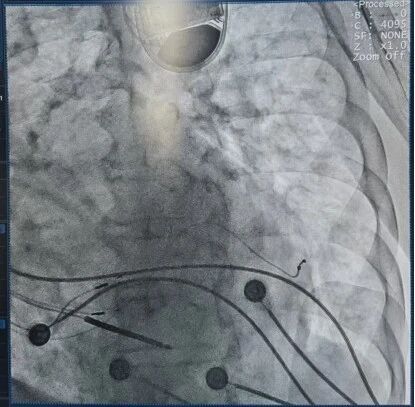

术前超声心动图提示:左心室扩大(LVEDD 78mm),射血分数(EF)仅31%;术前自身心电图提示QRS波时限210ms,完全性右束支传导阻滞合并室内阻滞。病情危重,常规治疗难以明显改善,需借助更先进的同步化电治疗技术。

针对患者非典型传导阻滞、既往起搏依赖等复杂情况,传统CRT方式难以获得理想的同步化效果,心内四科专家团队制定了LOT-CRTD(左束支区域起搏 + 左室多部位起搏)策略,以最大化再同步化获益。

?? 精准标测His电位及左束支电位,寻找最佳生理起搏点;

?? 在心肌纤维化及传导异常背景下反复定位,实现稳定左束支区域激动;

?? 成功植入左室电极并顺利到达后静脉上分支远段;

?? 术中测试达到了显著的再同步化效果。

术中指标显著改善,QRS时限由210 ms→160 ms;左束支区域起搏阈值仅 0.7 V @ 0.4 ms,参数稳定;左室电极起搏无脱落,无膈肌刺激,效果理想。手术安全、顺利完成。